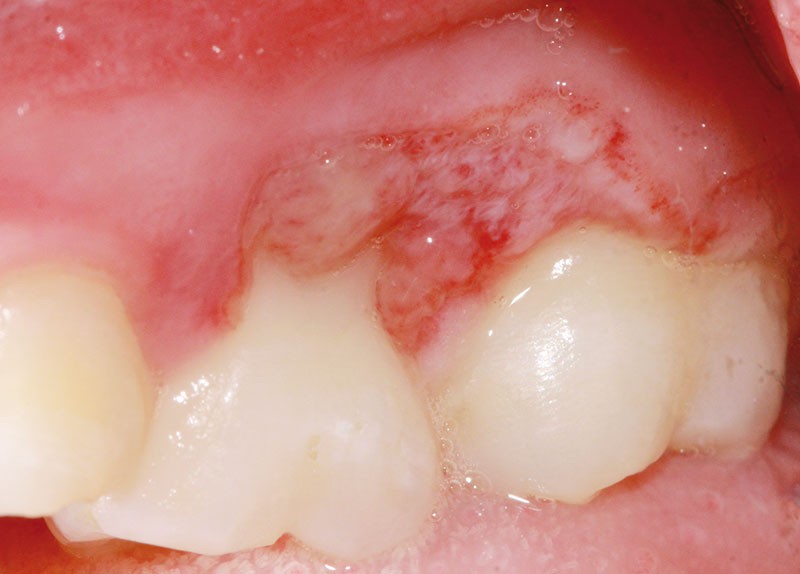

L’examen clinique révèle la présence d’une ulcération végétante, d’environ 1 cm de diamètre, localisée sur les gencives marginale, papillaire et attachée en vestibulaire de 55 et 16, associée à une récession parodontale pour 55. L’ulcération est bien délimitée, indolore et non hémorragique spontanément. Les dents présentent une mobilité physiologique et il n’existe pas d’adénopathie.

Lors du contrôle à une semaine, la situation clinique ne s’est pas améliorée et devant l’aspect…